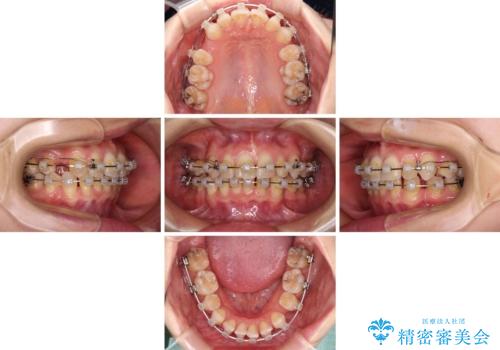

- クリアブラケット

- 3年8ヶ月

- 30回以上

アンカースクリューを用いて正中位置を調整したことで、上下の正中位置をほぼ一致させることができました。

移動量が多かったため、治療期間は長くなりましたが、大変満足のいく仕上がりとなりました。